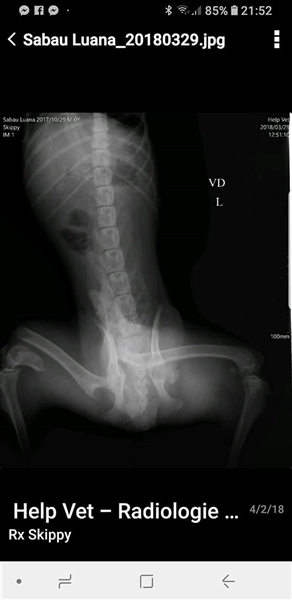

Skipper wurde im Oktober 2017 geboren, hat eine Schulterhöhe von knapp 50 cm und ist kastriert. Der Rüde wurde verletzt im Straßengraben gefunden, beide Hinterbeine waren gebrochen, doch er konnte erfolgreich operiert werden. Er ist inzwischen wieder flott auf seinen vier Beinen unterwegs, auch wenn sein Bewegungsablauf nicht ganz rund ist, so schränkt ihn seine minimale Behinderung nicht ein, fällt auch kaum auf und er ist auf seinen vier Beinen flott unterwegs. Der hübsche Rüde wird vielleicht nicht der ideale Begleiter für längere Joggingrunden oder Radtouren sein, aber nicht jeder Mensch ist ein Sportfreak und Skipper ist auf keinen Fall ein Couchpotato. Skipper lebt seit Juli bei einer Pflegefamilie in Dortmund zusammen mit anderen Hunden und kann dort gerne kennengelernt werden.